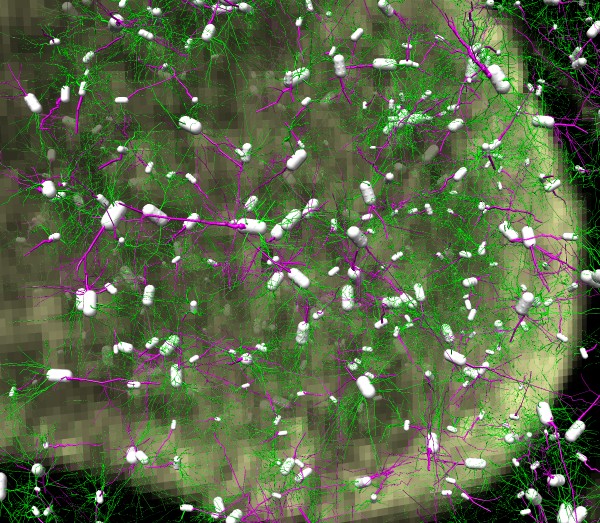

| Neuron trace

| 500 neurons, spread out

| Physiological density.

- Show 500 traced neurons at 10x normal spacing.

- Show 500 neurons at normal spacing, densely packed.